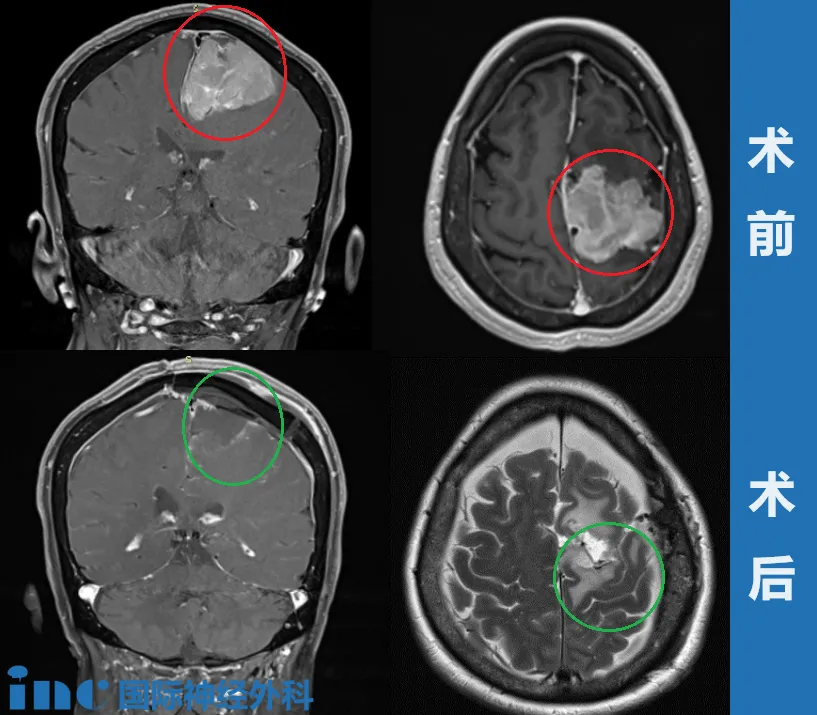

大脑镰旁巨大脑膜瘤,INC巴教授如何顺利全切

年过花甲的退休老师王女士因为患上“左侧额部大脑镰旁脑膜瘤”饱受愈演愈烈的头痛、癫痫、肢体无力的折磨,保守治疗已经令她痛苦不堪,可是由于肿瘤靠近大静脉窦和运动功能区,手术难以全切,易复发,且术后致瘫风险很大(60-100%不等)。

经过多次筛选和考量,王女士找到INC德国巴特朗菲教授。术前MRI显示左侧大脑镰旁巨大脑膜瘤,钙化和瘤周压迫、水肿效应明显。

巴教授为其进行左侧额叶到额顶叶旁矢状面的成骨性环锯术和显微外科脑膜瘤切除术、自体骨膜移植的硬脑膜成形术。

手术成功,肿瘤全切、矢状窦成功重建、运动功能区无损伤。术后影像显示肿瘤肉眼下全切,可见局部组织缺陷,水肿效应存在,被压迫正常脑组织缓慢复位。

术后第二天下午,王女士就能在医院护理人员的搀扶下进行走路康复训练。术后一周多已经恢复得和正常人一样,精神状态很好,可以在医院内自由散步,术后两周王女士顺利出院回国。